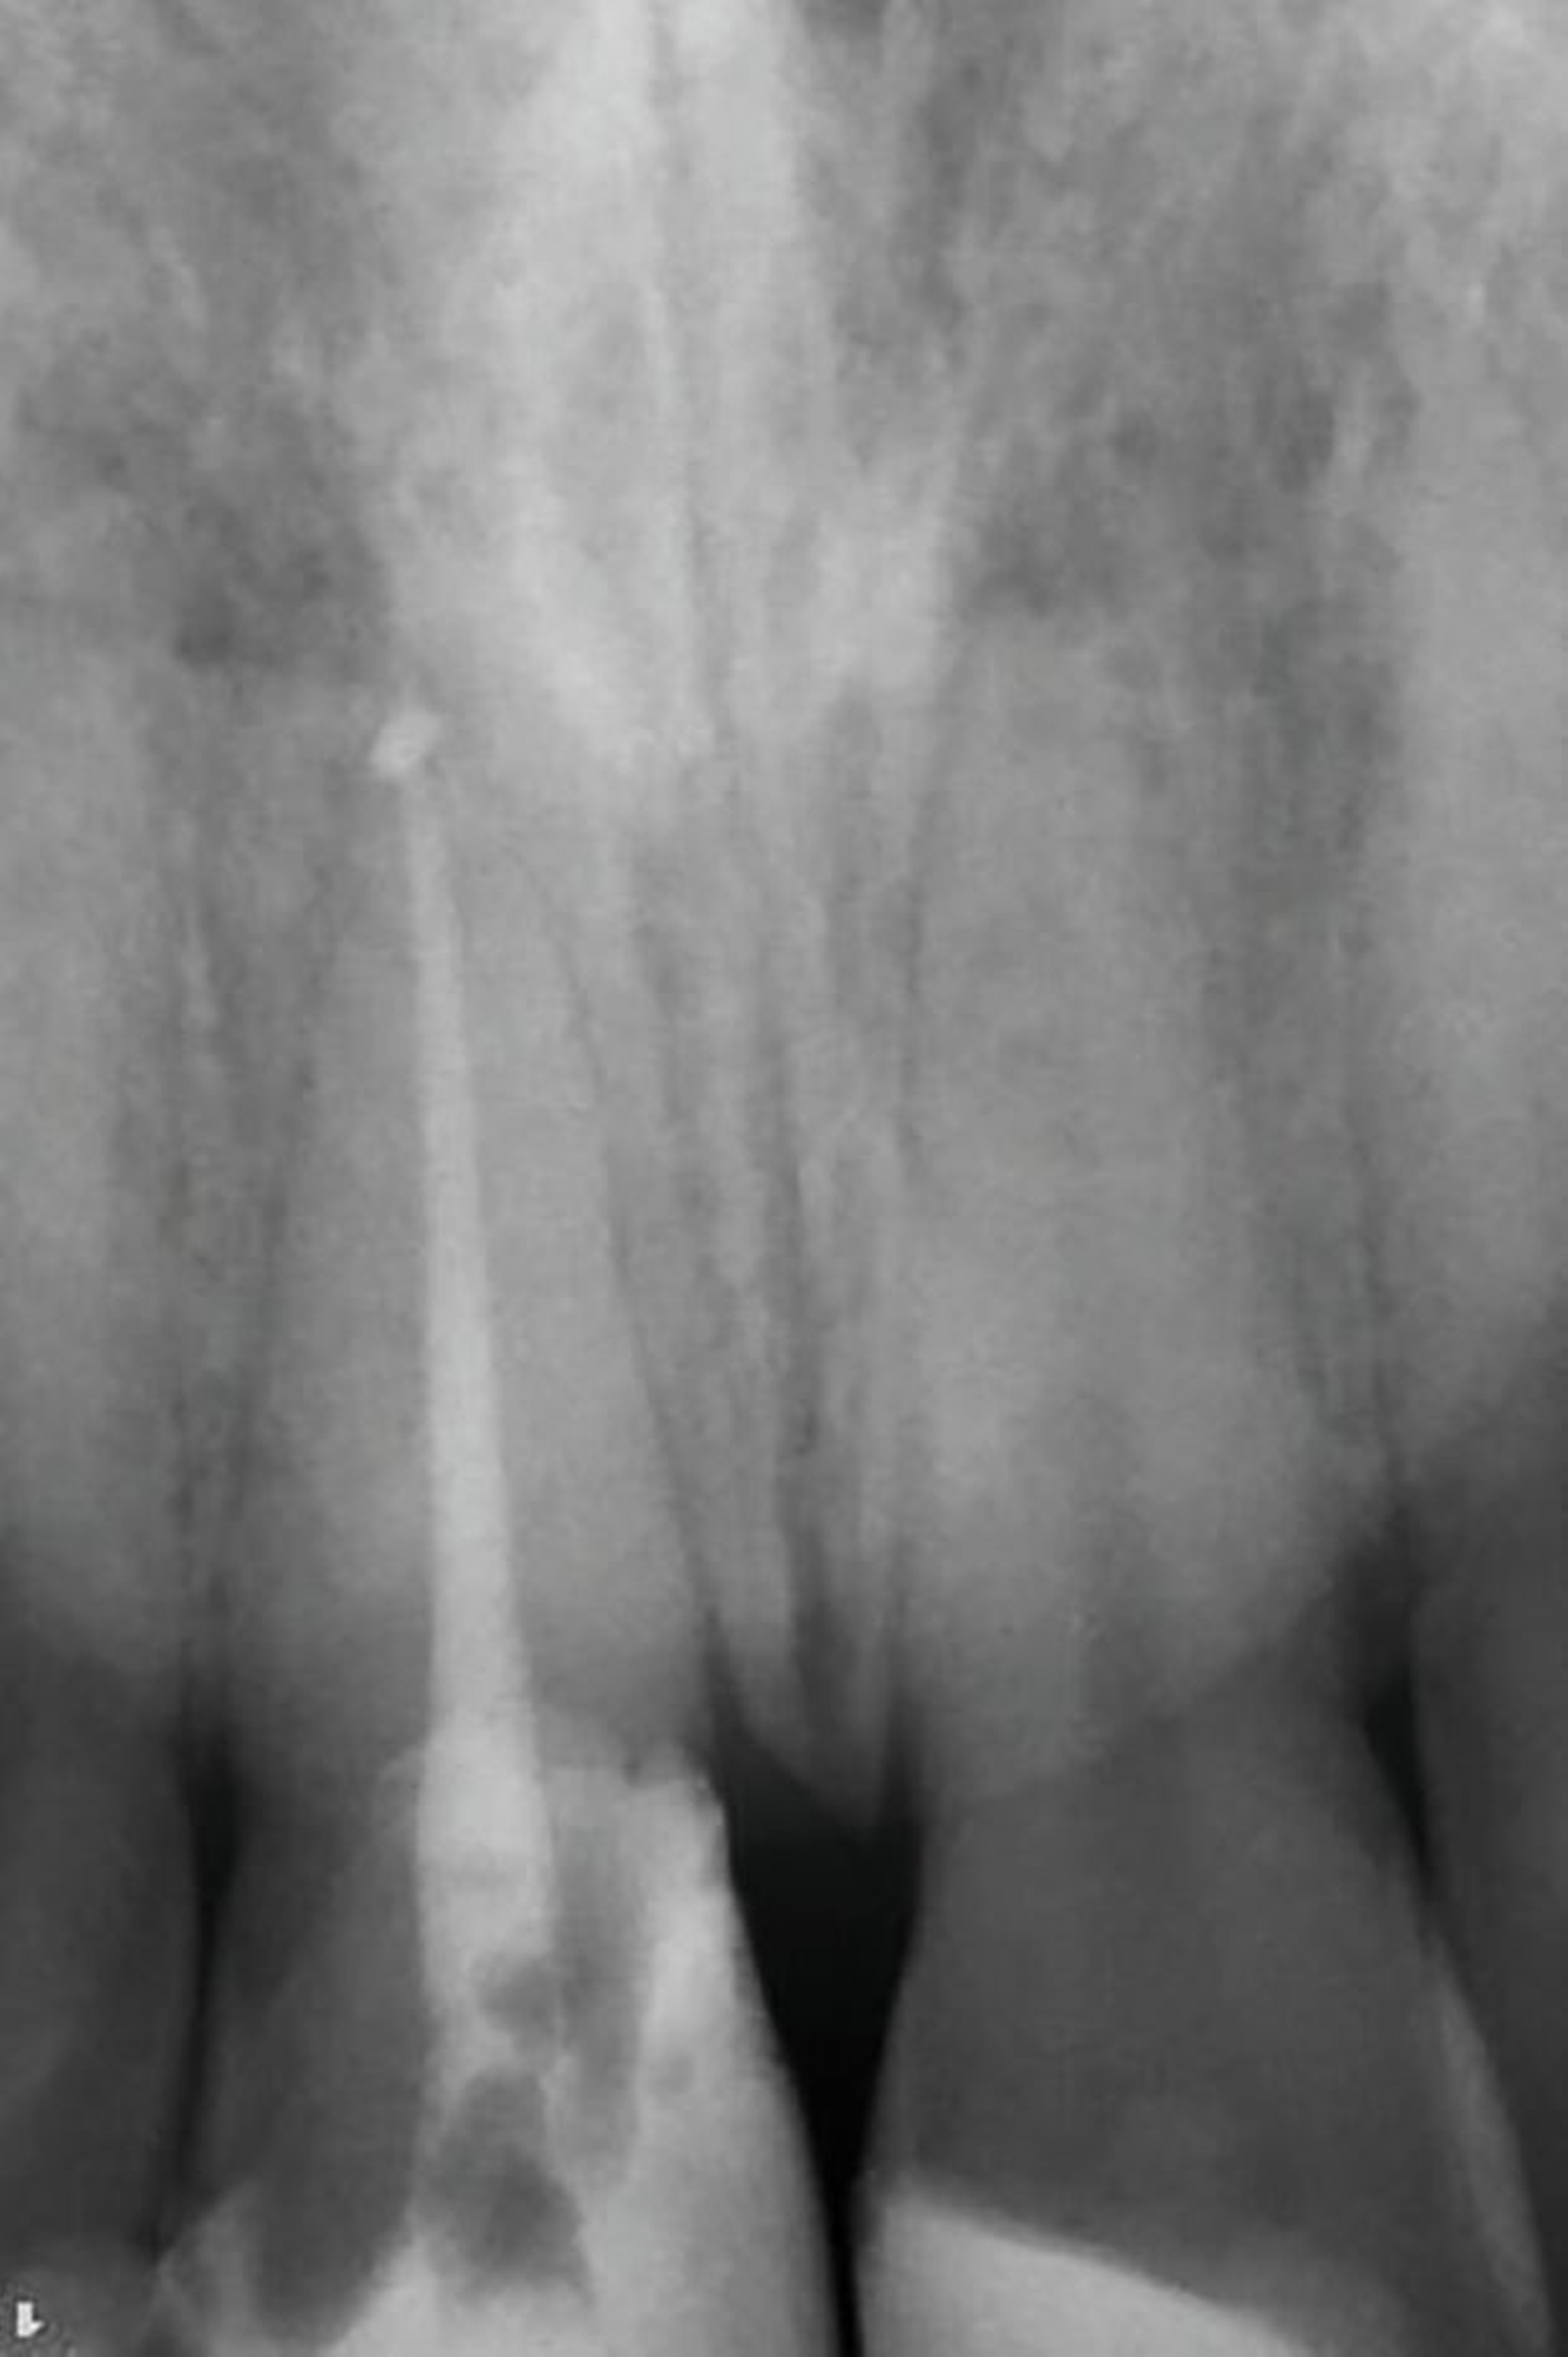

In der zwischenzeitlich angefertigten Einzelzahnaufnahme sind die orthopädisch bedingten Umbauprozesse anhand eines deutlich erweiterten Parodontalspalts und an der Verlagerung des Zahnes nach koronal zu erkennen (Abbildung 13). Auffällig ist, dass approximal ein Knochenumbau stattgefunden hat, was im Rahmen der kieferorthopädischen Extrusionstherapie zu erwarten war.

Nachfolgend konnte die Multibracket-Apparatur (MBA) für die Extrusion in Segmentbogentechnik befestigt werden (Abbildung 10). Dazu wurden die zu beklebenden Kompositflächen mit Aluminiumoxid-Pulver gestrahlt und mit einem Silan-haltigen Haftvermittler benetzt. Anschließend wurde drei Monate die kieferorthopädische Extrusionstherapie durchgeführt (Abbildungen 10 bis 12). Der Patient stellte sich wöchentlich zur Fibrotomie vor, um eine Verlagerung der Gingiva nach koronal zu vermeiden. Aufgrund der nach koronal gerichteten Bewegung erfolgte im Bedarfsfall das Einkürzen der Schneidekante.